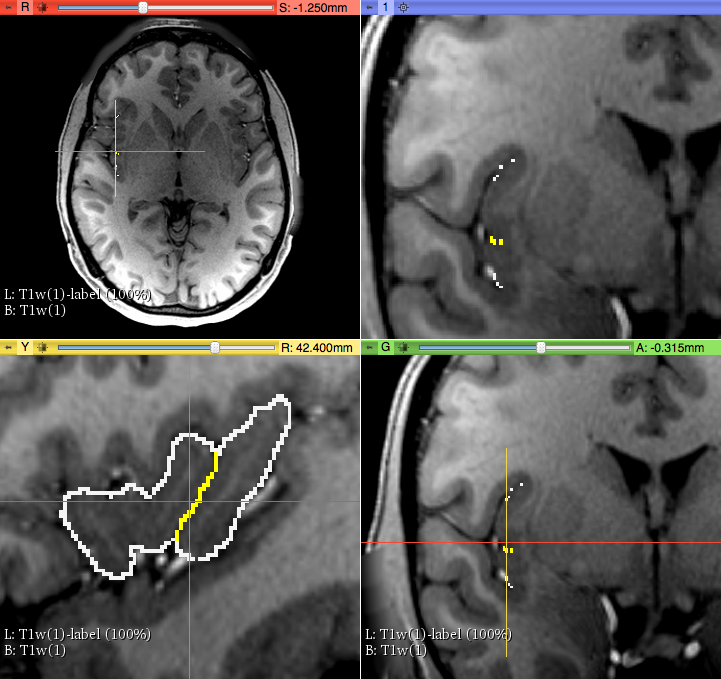

1) On a T1 MRI image, using the Segment Editor module, we used 3 segments (via “add” icon). The first segment was for the background, the second for the whole Insula and the third for the separation between the two subunits of the insula, i.e., aINS and pINS. To establish accurately the borders of aINS and pINS we traced the Circular sulcus and the Central sulcus of the Insula as follows. First, we used three sagittal images where these sulci were visually well-identifiable. Consequently, these sulci were detected on coronal sections as a series of dots, which served as our key anatomical landmarks for the segmentation of aINS and pINS. More specifically, the circular sulcus of the insula determined the outer boarder of the insula in its entirety and the the Central sulcus (cesi) determined the for border between anterior and posterior Insula (coronal view).

Circular Sulcus (white) and Central Sulcus (yellow) in the parcellation method of anterior and posterior Insula